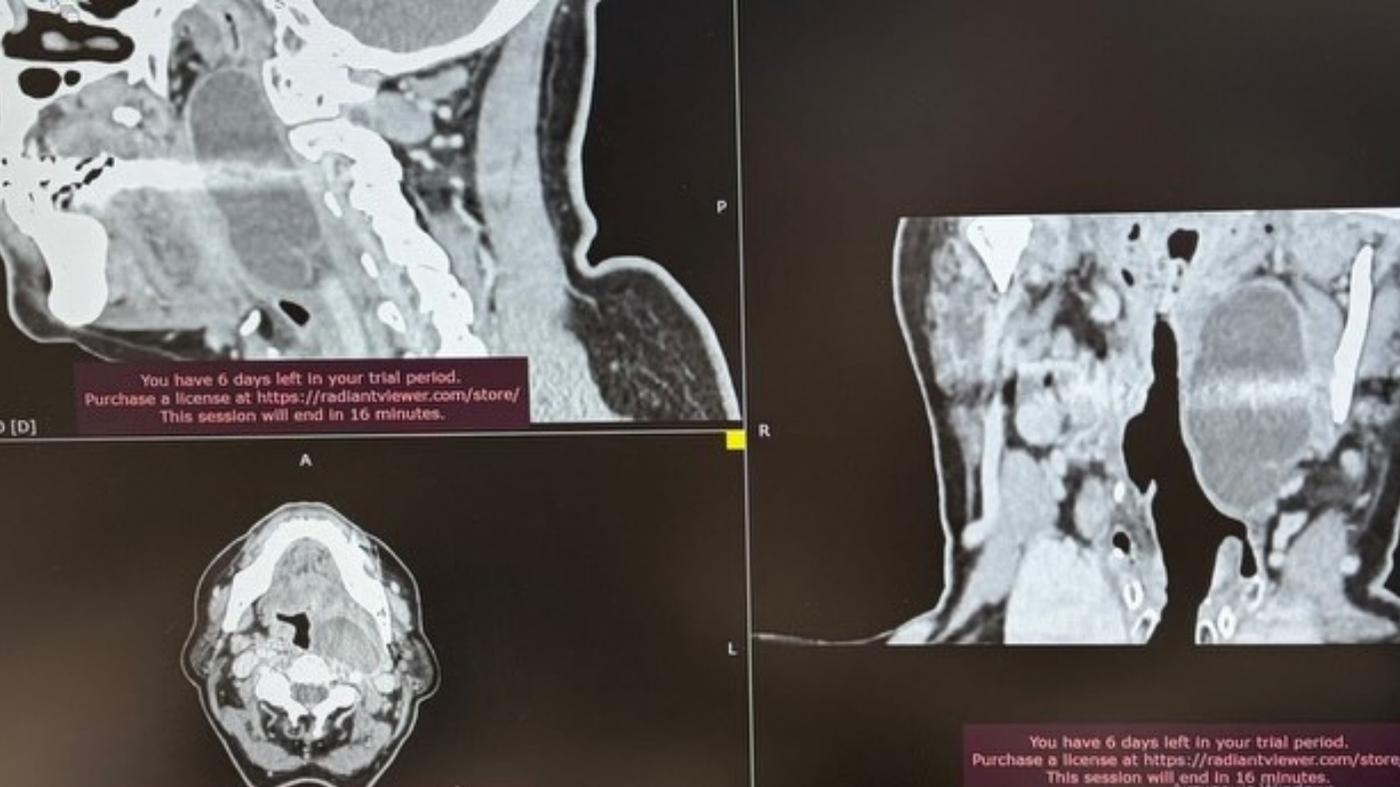

Успішно виконали складне хірургічне втручання з приводу рідкісної пухлини парафарингеального (позаглоткового) простору. Пухлини цієї локалізації трапляються відносно нечасто. Вони можуть тривалий час залишатися майже непомітними, однак зі збільшенням розмірів починають викликати виражені симптоми через близькість до важливих анатомічних структур, — йдеться у повідомленні.

У цьому випадку пухлинне утворення досягло значних розмірів і почало утруднювати прийом їжі та дихання, що потребувало оперативного лікування.

Зважаючи на анатомічну складність цієї ділянки та близькість магістральних судин і нервових структур, лікарі провели ретельне передопераційне планування. Операцію виконана у плановому порядку, і пухлинне утворення вдалося повністю видалити.